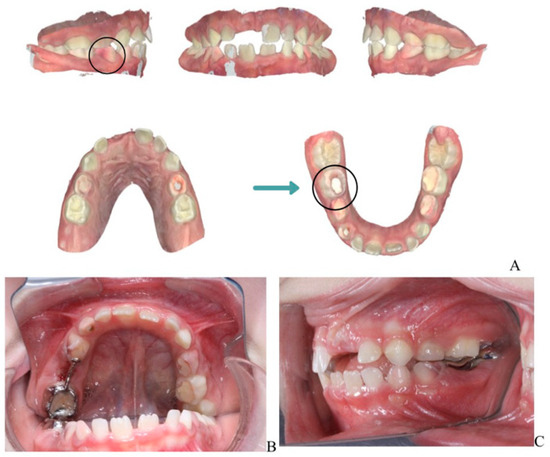

Clinical Management of Cervical Restorations with Closing Gap Technique: A Follow-Up of Two Cases

Background: Cervical restorations remain clinically challenging due to complex anatomy, limited enamel availability, and difficulties in achieving reliable adhesion at dentin or cementum margins. Polymerization shrinkage and marginal leakage are frequent causes of failure. Although the Closing Gap Technique has been proposed to [...] Read more.

Background: Cervical restorations remain clinically challenging due to complex anatomy, limited enamel availability, and difficulties in achieving reliable adhesion at dentin or cementum margins. Polymerization shrinkage and marginal leakage are frequent causes of failure. Although the Closing Gap Technique has been proposed to improve marginal adaptation in cervical restorations, evidence supporting its medium- to long-term clinical performance is limited. The aim of this case report was to evaluate the clinical effectiveness of the Closing Gap Technique in the restoration of carious and non-carious cervical lesions. Materials and Methods: Two patients presenting with cervical lesions were treated using the Closing Gap Technique. One case involved carious cervical lesions, while the second included multiple non-carious cervical lesions. Restorations were performed following an enamel-anchored incremental layering protocol with resin composite. Clinical evaluations were conducted at 8 years (case #1) and 2 years (case #2) post-treatment, respectively. Results: Both cases demonstrated favorable clinical outcomes at follow-up. The restorations exhibited good marginal integrity, satisfactory esthetics, absence of marginal discoloration, no secondary caries, and no signs of debonding. The only minor defect observed was slight chipping of one of the restorations. Conclusions: Within the limitations of this case report, the Closing Gap Technique showed stable and predictable medium- and long-term clinical performance, supporting its use as a viable restorative approach for managing cervical lesions in daily clinical practice. Full article